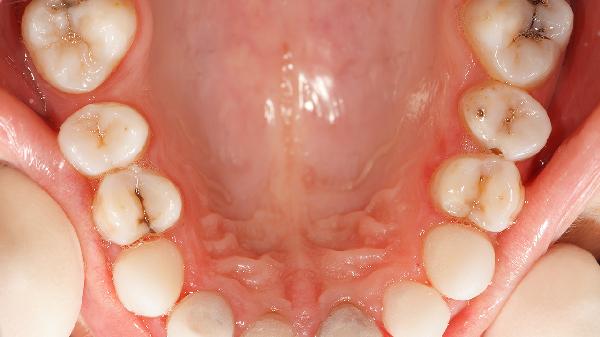

牙齿脱矿早期可以通过再矿化治疗恢复,但严重脱矿导致牙体缺损时需医疗干预。牙齿脱矿主要与口腔清洁不足、酸性饮食、唾液分泌减少、正畸治疗、胃酸反流等因素有关。

长期刷牙不彻底会导致牙菌斑堆积,细菌代谢产酸侵蚀牙釉质。表现为牙齿表面白垩色斑块,可能伴随牙龈出血。可使用含氟牙膏配合巴氏刷牙法,医生可能建议局部涂布氟化钠凝胶或使用氯己定含漱液抑制菌斑。家长需监督儿童每日刷牙两次,每次不少于两分钟。

固定矫治器周围易滞留食物残渣形成脱矿白斑,多发生于托槽周围牙龈缘上方。需使用正畸专用牙缝刷清洁,配合含氟泡沫预防,严重者需拆除矫治器后行渗透树脂治疗或微研磨处理。